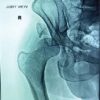

Figure 5: (a) Chondrolysis of the entire acetabular cartilage; (b) Intraoperative image showing use of small reamer to medialise the acetabular cavity and reduce the fractured inturned acetabular wall; (c) Intraoperative image showing managing interaoperative fracture with encerclage; (d) Fluoroscopic image showing placement of acetabular and femoral component with encerclage.

Step 4: Preparation for stem insertion

The femoral shaft was exposed for stem preparation. Initially, broaches for uncemented stems were used, but the femur was very osteoporotic, and the decision to put a cemented stem was taken. After broaching the canal, a trial was done after putting a small stem without a head to assess reducibility. Initially, even this was very difficult, and sustained traction was used to reduce the stem. Traction was continued for 10 min even after reduction, to gradually stretch the tissues. The knee joint was flexed to reduce sudden traction injury to the sciatic nerve. The trial stem and head were dislocated using a bone hook. Being a tight reduction, it was difficult to dislocate, and sustained traction with a bone hook was used to dislocate it. However, we encountered a medial calcar fracture on the anterior surface after removing the femoral stem. The fracture line extended nearly an inch below the calcar. Encerclage wires were used to prevent any further propagation of the fracture (Fig. 5c). The stem was then cemented using compression of the fracture with bone holding forceps. Extravasated cement was removed. No trial reduction was done to prevent any further fractures of the osteoporotic bone. Final reduction was done with a small-sized head, and the limb was put in flexion at the knee to prevent sciatic nerve injury, and then gradually straightened the leg (Fig. 5d).

Figure 6: (a) Post-operative plain radiograph; (b) Clinical photograph of patient: (c) Follow-up 1-month plain radiograph; (d) Follow-up 1-month clinical photograph of patient.

Fig. 6a and b shows the patient post-operative plain radiograph and clinical picture.

Fig. 6c and d shows the patient follow-up plain radiograph and clinical picture after 1 month.